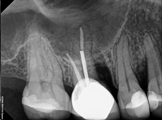

Conventional Endodontic Treatment/Retreatment with Prefabricated Bonded Post and Core

Conventional Endodontic Treatment with Minimal Clinical Crown: Cast Post and Core Coronal Restoration